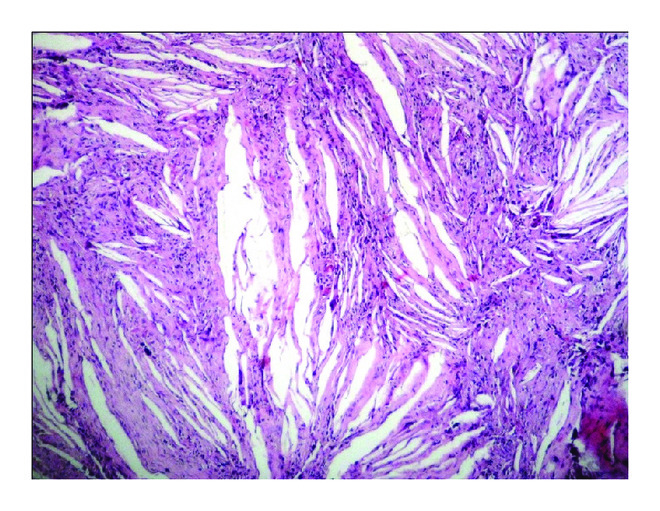

A 45-year-old male reported to the institute with the complaint of swelling in the posterior tooth region of right maxilla since one month. Patient gave a history for the extraction of 17, 18 (with grade II mobility) for the same in private dental clinic but after extraction the swelling persisted. On palpation, swelling was soft and fluctuant in nature extending from the buccal vestibule till midline of the hard palate. FNAC was attempted but the mass bled profusely. CT scan revealed a huge expansile, well demarcated, and osteolytic mass extending from maxilla into the maxillary sinus. A provisional diagnosis of keratocystic odontogenic tumor (KCOT) was made. Surgical enucleation of the cyst was performed and the tissue was sent for histopathological examination. The sections revealed proliferation of cystic odontogenic epithelial lining with palisaded hyperchromatic columnar nuclei, stellate reticulum like areas, and sheets of abundant ghost cells. Surrounding connective tissue stroma showed mature collagen bundles. Abundant hemorrhagic areas and fibrin deposits were evident both in fibrous wall and in cystic lumen. Also visible both in the connective tissue and in cystic lumen were abundant cholesterol clefts and hemorrhagic areas. Focal areas of ghost cell formation were also visible in the stroma surrounded by foreign body giant cells and hemosiderin pigmentation. Thus, based on this a final diagnosis of calcifying odontogenic cyst with cholesterol granuloma was made (Figure 1).

(a)

(b)

(c)

(d)